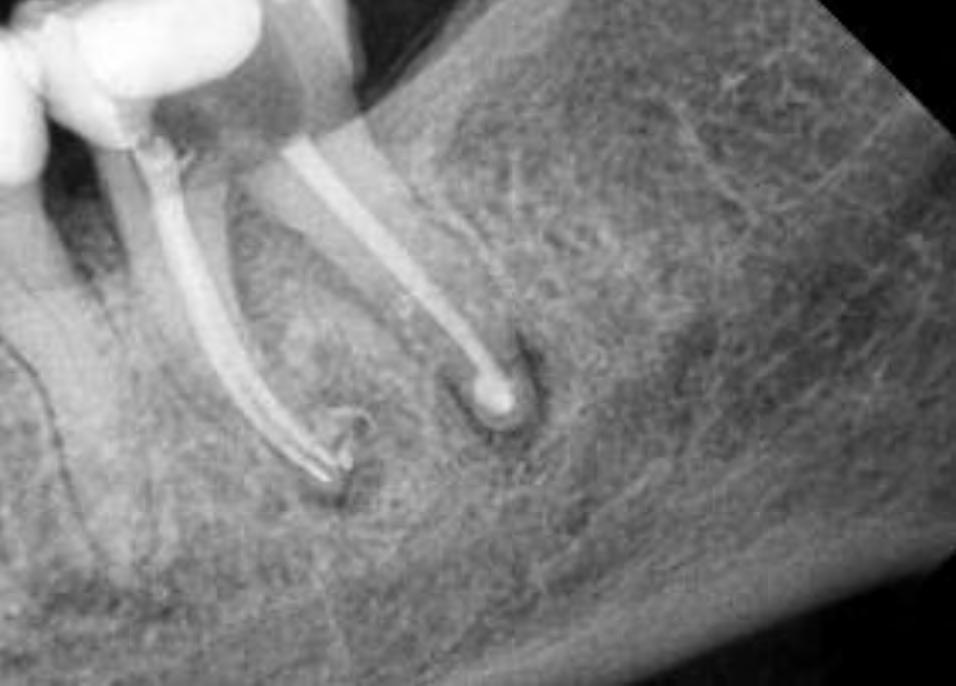

Looking at this pre-operatory radiograph, two information regarding this endodontic case should be detected (Fig.1):

Case Report Fig.1

Followed shaping of coronal and middle part, WL was determined with K-File #10 and shaping procedure were completed with martensitic X7 (EdgeEndo, Albuquerque, NM) instruments in sizes 17 and 25, .04 taper. The instruments were used with a reciprocating motion (150-30) to increase resistance to both torsional and flexural stress (fig.2)

Fig.2

The root canal system was rinsed, dried and then obturated with an hydraulic single cone-technique and bioceramic sealer (BUSA, BC Sealer). Two periapical radiographs with different angulations were taken to verify treatment quality (Fig.3-4).

Clinician’s suspect of unusual anatomy of the distal root anatomy was confirmed by the angulated radiograph that showed an abrupt hidden curvature in the apical third of the canal. Nevertheless the crown-down approach (shaping the coronal and middle part first, thus reducing coronal interferences) and the Fig.3 Fig.4

proper selection of very flexible and resistance instruments, combined with a safer reciprocating clinical motions, allowed to properly negotiate the hidden curvature with no iatrogenic errors . The X7 instruments were chosen because their innovative manufacturing process which provides them with unprecedented flexibility and resistance to cyclic fatigue, allowing practitioners to perform procedures that would be difficult, if not unimaginable, with traditional non-heated files. More precisely, EdgeEndo has focused research and development in the heat-treatment of NiTi files and has developed a proprietary process to produce FireWire™ files that exhibit 2 to 8 times the resistance to cyclic fatigue (and flexibility) than other NiTi files. The benefits of a flexible file seem obvious in complex curvature, but martensitic X7 files also offer another advantage: less “shape memory”. Although shape memory may seem beneficial, it can cause a file to “bounce back” in the tooth, putting lateral pressure on the canal wall, potentially leading to canal transportation or ledging. The present case shows how the excellent clinical performance of X7 files in a very complex anatomy, by avoiding the above mentioned , common iatrogenic errors.